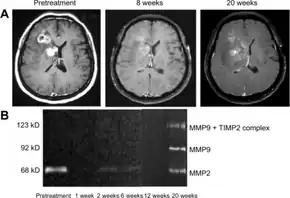

Bevacizumab slows tumor growth but does not affect overall survival in people with glioblastoma multiforme.[25] The FDA granted accelerated approval for the treatment of recurrent glioblastoma multiforme in May 2009.[26][27] A 2018 Cochrane review deemed there to not be good evidence for its use in recurrences either.[25]